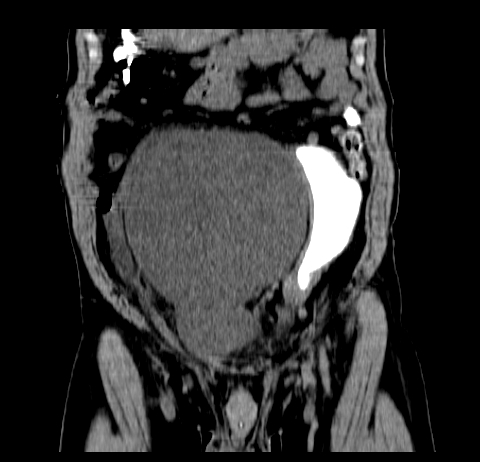

标题: CT19729B:男,74岁,因腿疼就诊,查体触腹部肿物,

增强扫描

动脉期

【ct表现】

1、肿块巨大,往往位于腹膜后,长大后才引起症状而就诊;那么位于腹膜后的肿瘤80%为恶性肿瘤。

2、实性肿瘤,增强扫描轻度不均强化,实性肿瘤一般不是好东西。

3、肿瘤边缘似见少许脂肪样密度。

4、腹膜后未见肿大淋巴结,但肿瘤于临近的肠管及组织接触紧密。

【诊断】

腹部占位,考虑位于腹膜后的恶性肿瘤,脂肪肉瘤(实体型)可能性大。

应该是腹腔病变,病灶较大,内可见脂肪密度影,边界较清,有钻孔样改变,表皮强化,考虑畸胎瘤(皮样囊肿)可能性大.

术后病理结果:腹膜后脂肪肉瘤。